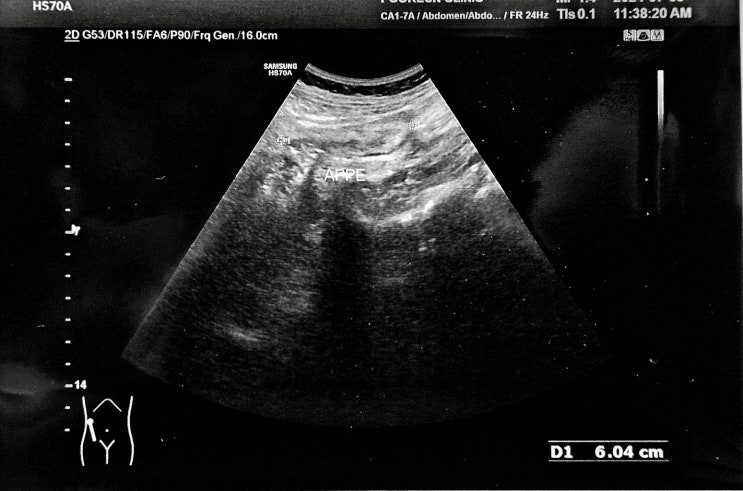

복통을 동반 한 담석증 45세 여자. 밤새 윗배가 아팠다며 내원. 특히 잠을 못잘정도로 많이 아팠다고 한다....